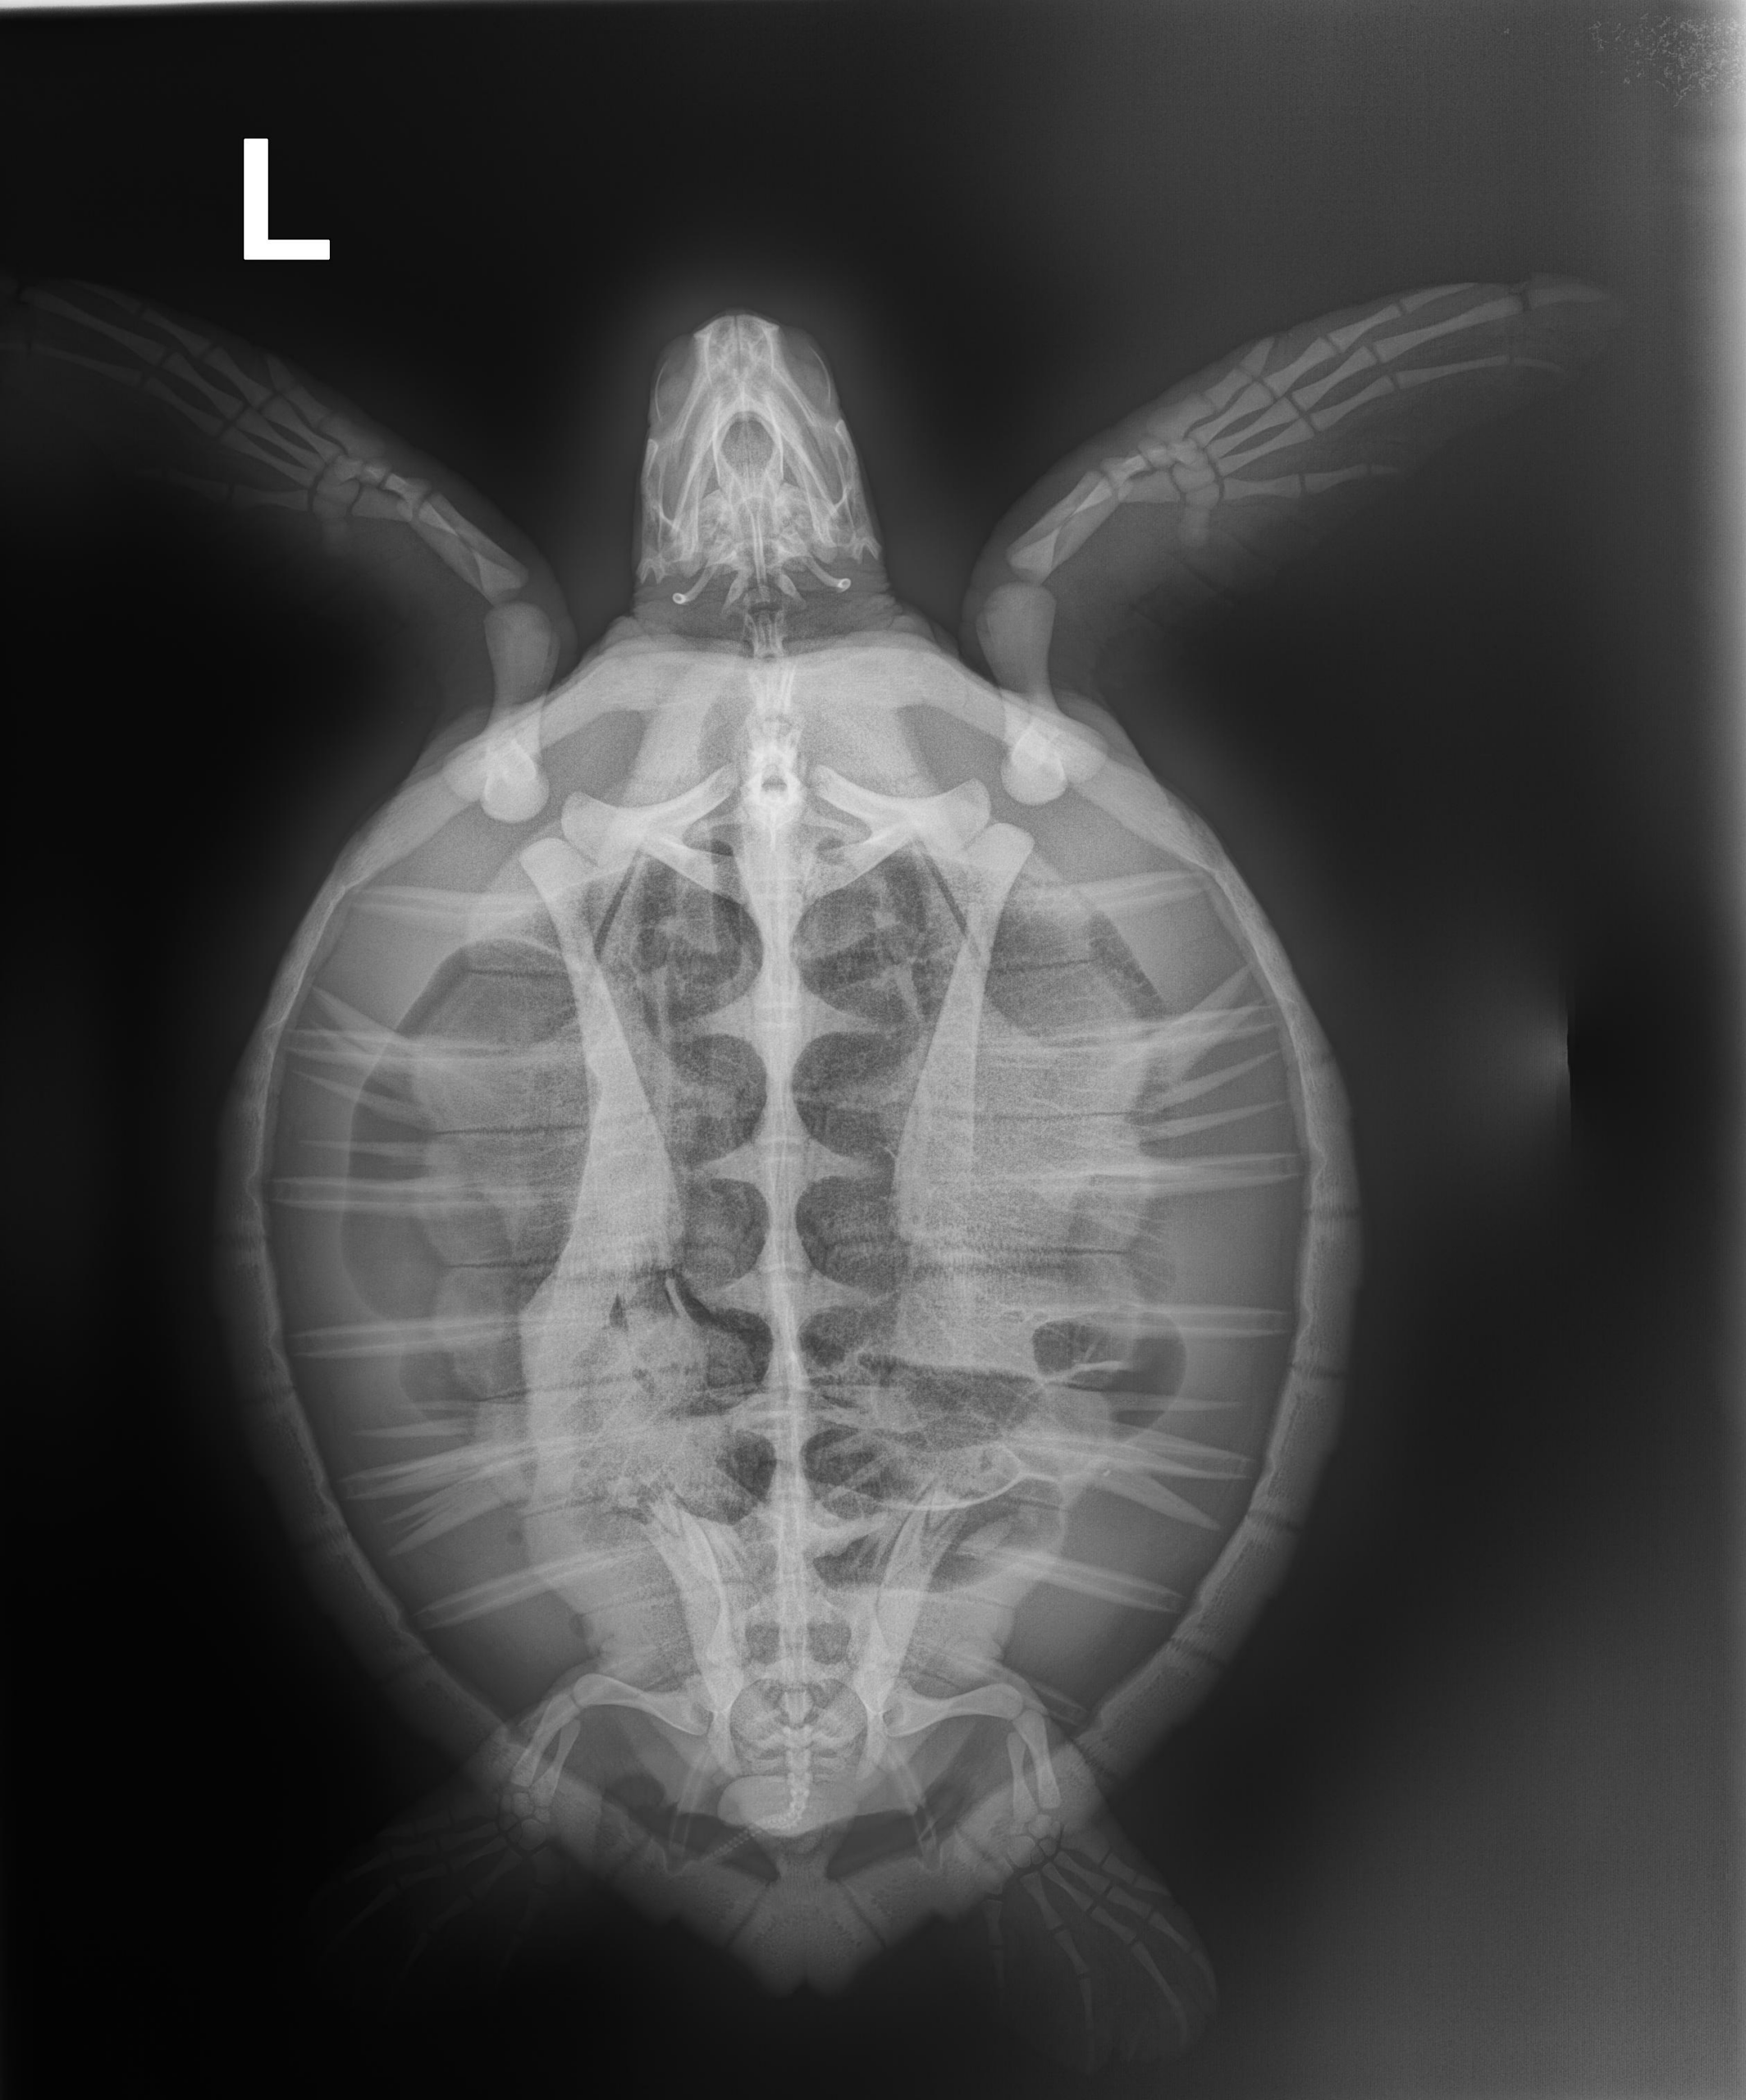

4.8 lbs/ 2.2 kg Atlantic Green Turtle non FP

Moderate abrasions on carapace and flippers, severe abrasions on plastron, strange pink in both eyes